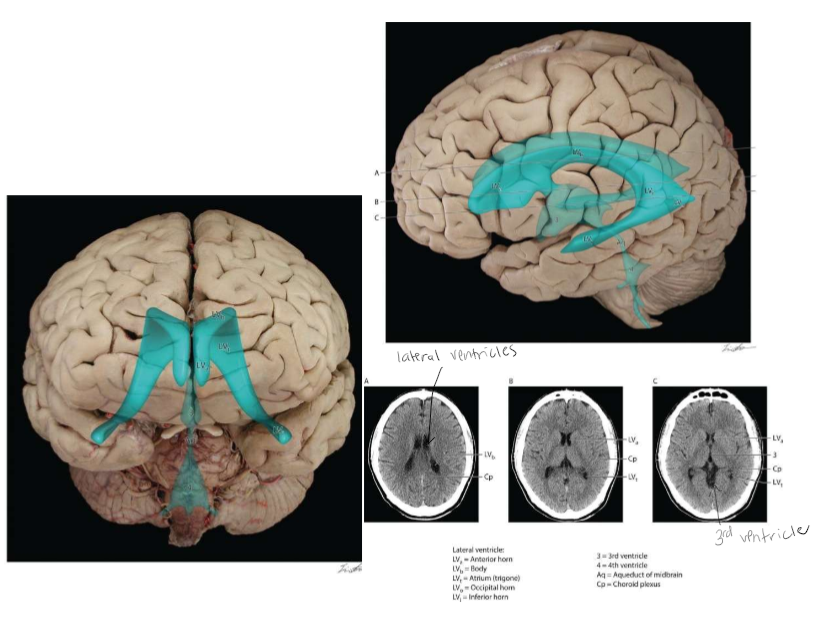

One brain structure, three different views

Spaces are lateral ventricles

The Ventricles

Cerebral Spinal Fluid (CSF) and the Ventricles

CSF is a clear fluid, similar to blood plasma. Formed in the choroid plexus. Foind in each lateral ventricle and the third and fourth ventricle. Composed of cuboidal epithelial cells resting on a basal lamina which are adjacent to highly fenestrated blood vessels separated by the stroma (lots of blood flow there). The tight junctions located between the apical parts of the choroid plexus epithelial cells form the blood-cerebrospinal fluid barriers (separation between 2 systems). CSF flows from the lateral to third to fourth ventricle to central canal or between meninges. CSF reabsorbed in arachnoid space between meninges and brain and spinal cord. CSF circulating at all times.

The Ventricular System

Cerebrospinal Fluid Circulation

red wave = choroid plexus. Foramen of Monro = connects lateral ventricle to 3rd ventricle. Central canal space surrounding spinal cord. In between meningal layers. CSF goes down and comes back up in subarachnoid space meningal layer.